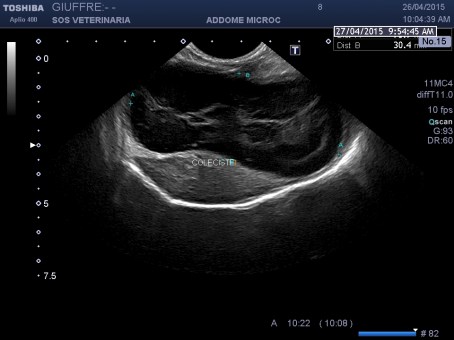

Cane femmina di bassotto di 6 aa presentata al pronto soccorso con vomito incoercibile ,profondo abbattimento ,mucose subitteriche ,no febbre,addome palpabile ,insorgenza dei sintomi iperacuta, l’ecografia addominale ha focalizzato una colecistopatia caratterizzata da severa distensione dell’organo , contenuto interno incrementato in ecogenicita’con formazione di una figura ecogena irregolare a pattern stellato (tipo Kiwi ) maggiormente evidenziabile con la sonda lineare frequenza ,pareti normali ,lieve falda di fluido tra parete e fossetta epatica ,evidente ectasia del dotto biliare comune , dotto cistico non evidenziabile per il grado di distensione elevato della coleciste ,nessun pattern riferibile a pancreatite o neoplasie della papilla,.il doppler colore evidenziava nei vasi portali un flusso a mosaico, che non scompariva all’aumento del PRF la mancata pulsatilita’ del pattern lo distingueva dal fenomeno dell’arteriolarizzazzione comune nelle epatiti tuttavia tale flusso non descritto in letteratura indicava certamente un’alterazione vascolare del parenchima come poi ha confermato il decorso clinico e non una semplice colastasi La ceus ha confermato la natura avascolare del contenuto e non ha fornito ulteriori indicazioni